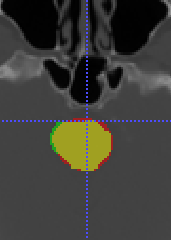

To model , we propose using a half-Gaussian distribution based on nodule size distribution because is correct if it is within the nodule area (center slice of as , and nodule size can be empirically estimated based on existing data) for nodule detection in Fig. 17(a). For lung lobe prediction , a logistic regression model is used based on relative value of nodule center after lung segmentation. That is

| (22) |

where is the associated weights with lobe location for logistic regression, feature , and is the total size of image after lung segmentation. In the experiments, we found the logistic regression converges quickly and is stable.